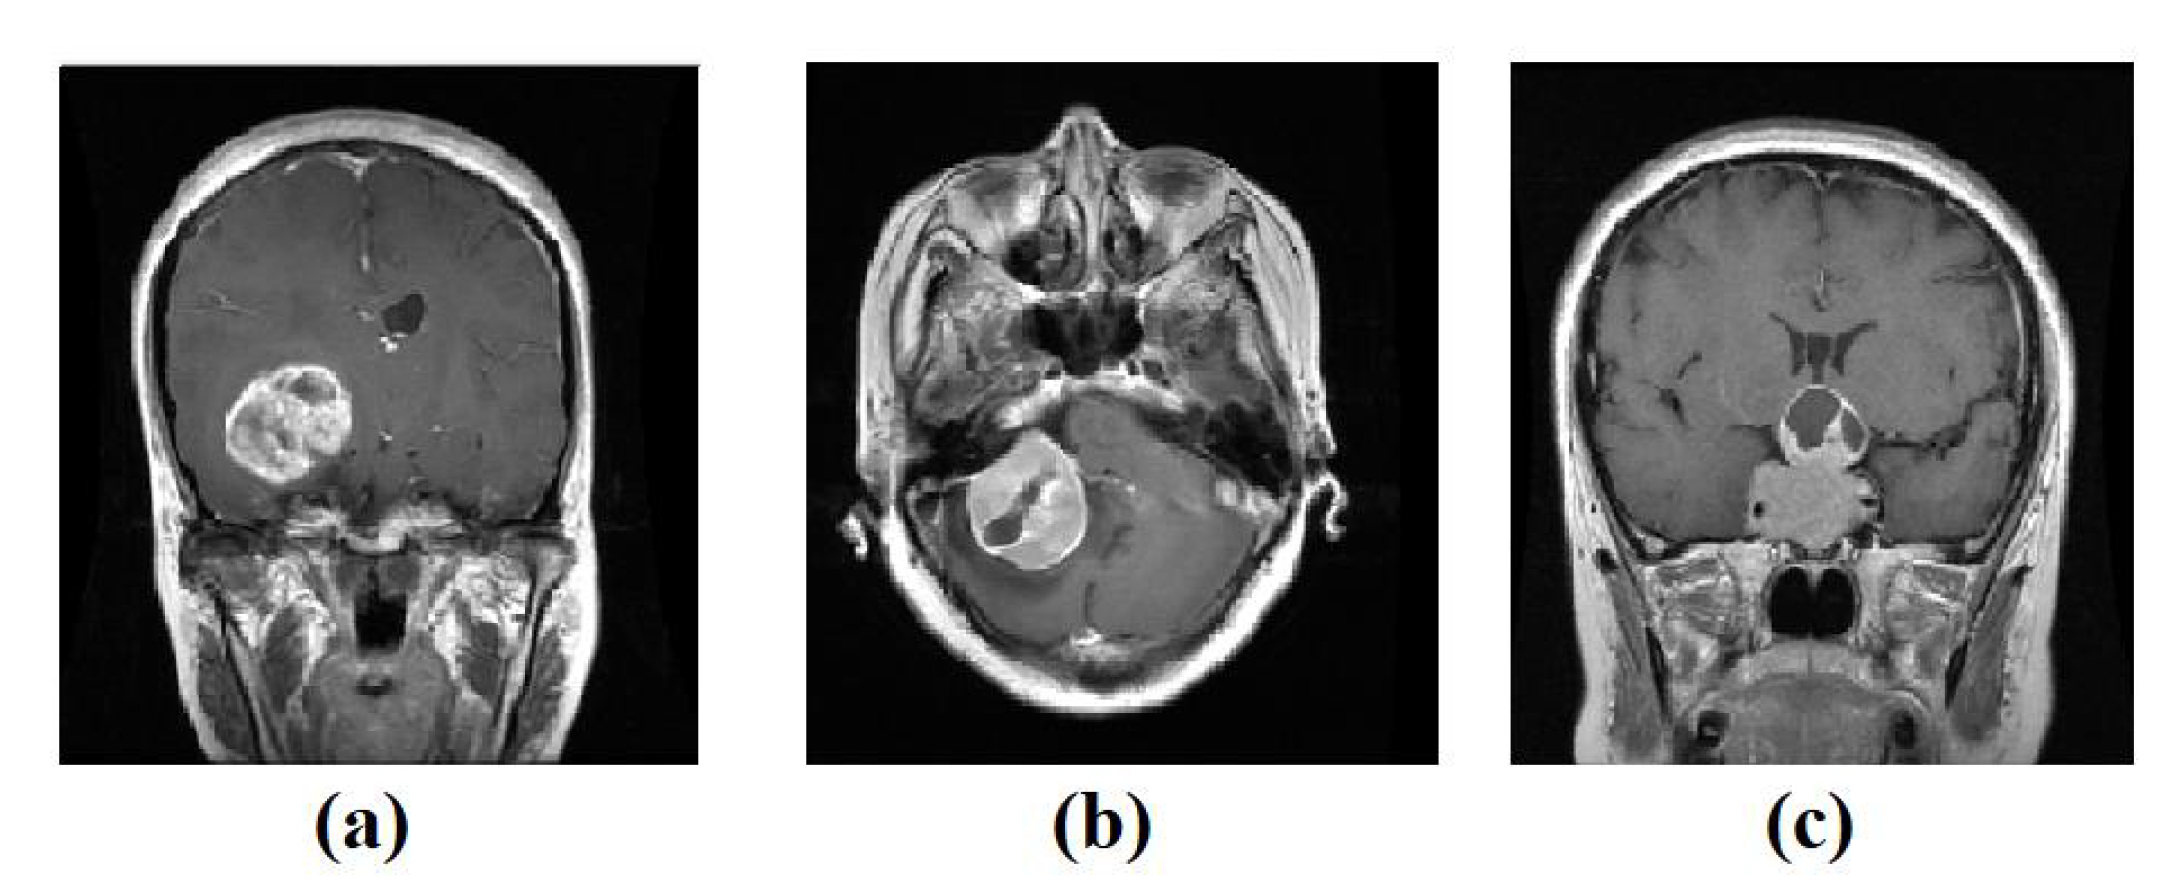

- For the labelled dataset, we have used a set of 3064 brain tumours from Nanfang and General Hospitals, Tianjin Medical University, China: 1426 glioma, 708 meningiomas, and 930 pituitary tumour, available from [59], all images with size 400 × 400 pixels. The training set was randomly divided into 60% to fit the model, 20% for validation, and 20% as a test set, see Table 2. Figure 3 shows examples of images from the test set.Table 1. The distribution of Colorectal cancer dataset.